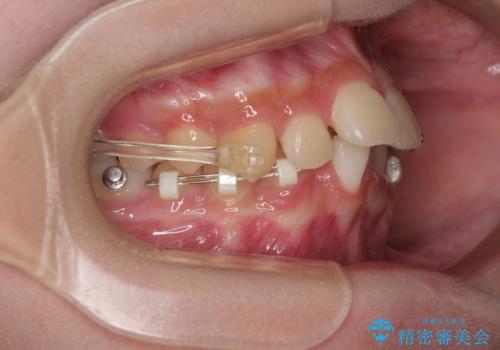

インビザライン単体で対応ることも検討できますが、達成する可能性が低いため、カリエールディスタライザーという補助装置を併用して、より確実性を上げることとしました。

奥歯の咬み合わせと深い咬み合わせを改善した後、インビザラインで歯列を整えることとしました。

ワイヤー装置と補助装置を有効に活用し、さらには高校生ということもあり、1年9か月で狙い通りの仕上がりを達成することができました。